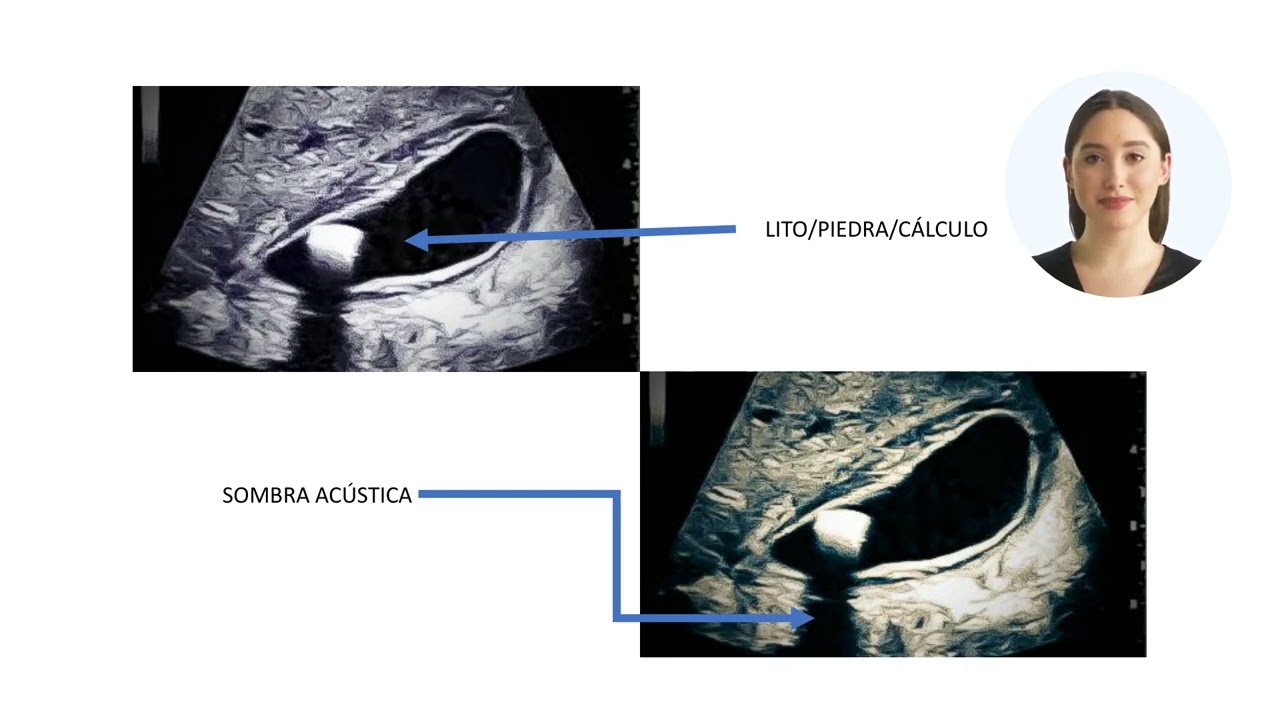

Cálculos biliares

La vesícula biliar almacena la bilis que el cuerpo utiliza para digerir las grasas. Cuando deja de funcionar, la bilis se torna espesa produciendo un lodo o incluso cálculos que llegan a bloquear los conductos causando irritación y aumento de la presión dentro de la vesícula biliar. El síntoma principal es dolor en la parte superior del abdomen, distensión, gases (eructos o flatulencia) náuseas y/o vómitos. En algunos casos coloración amarillenta o incluso fiebre. El tratamiento de elección es la cirugía laparoscópica temprana. Factores predisponentes incluyen embarazo, terapia hormonal, edad avanzada, historia familiar, subir o bajar de peso rápidamente, diabetes y otras enfermedades.